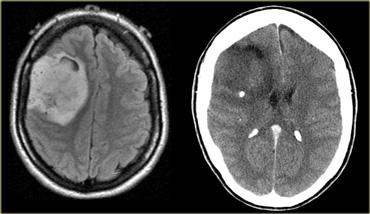

Bên trái là hình ảnh của một khối u trong trục ở người lớn.

Khối u có trung tâm ở thùy thái dương và xâm lấn vỏ não.

Mặc dù có sự phát triển thâm nhiễm lan rộng liên quan đến phần lớn bán cầu não phải, hiệu ứng khối chỉ ở mức tối thiểu.

Không có ngấm thuốc.

Các đặc điểm này điển hình cho u sao bào độ thấp.

Bên trái là hình ảnh của một khối u nằm ở bán cầu não phải.

Mặc dù là khối u lớn nhưng hiệu ứng khối còn hạn chế.

Điều này cho thấy có sự phát triển thâm nhiễm rõ rệt, đặc điểm điển hình của u thần kinh đệm.

Lưu ý tính không đồng nhất trên cả chuỗi xung T2W và FLAIR.

Có ngấm thuốc không đồng nhất dạng đốm.

Tất cả các đặc điểm này điển hình cho GBM.

Hầu như không có khối u nào khác có biểu hiện tương tự như vậy.